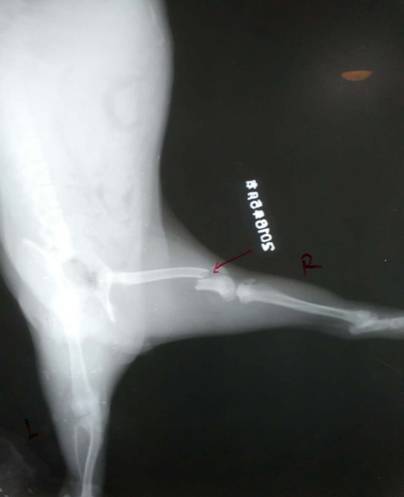

汝陽縣城英斗犬,球球,母,四月齡,右后肢股骨遠端骨折,進行整復手術。

骨折部位X光片顯示病肢股骨遠端橫斷骨折,進行手術治療。